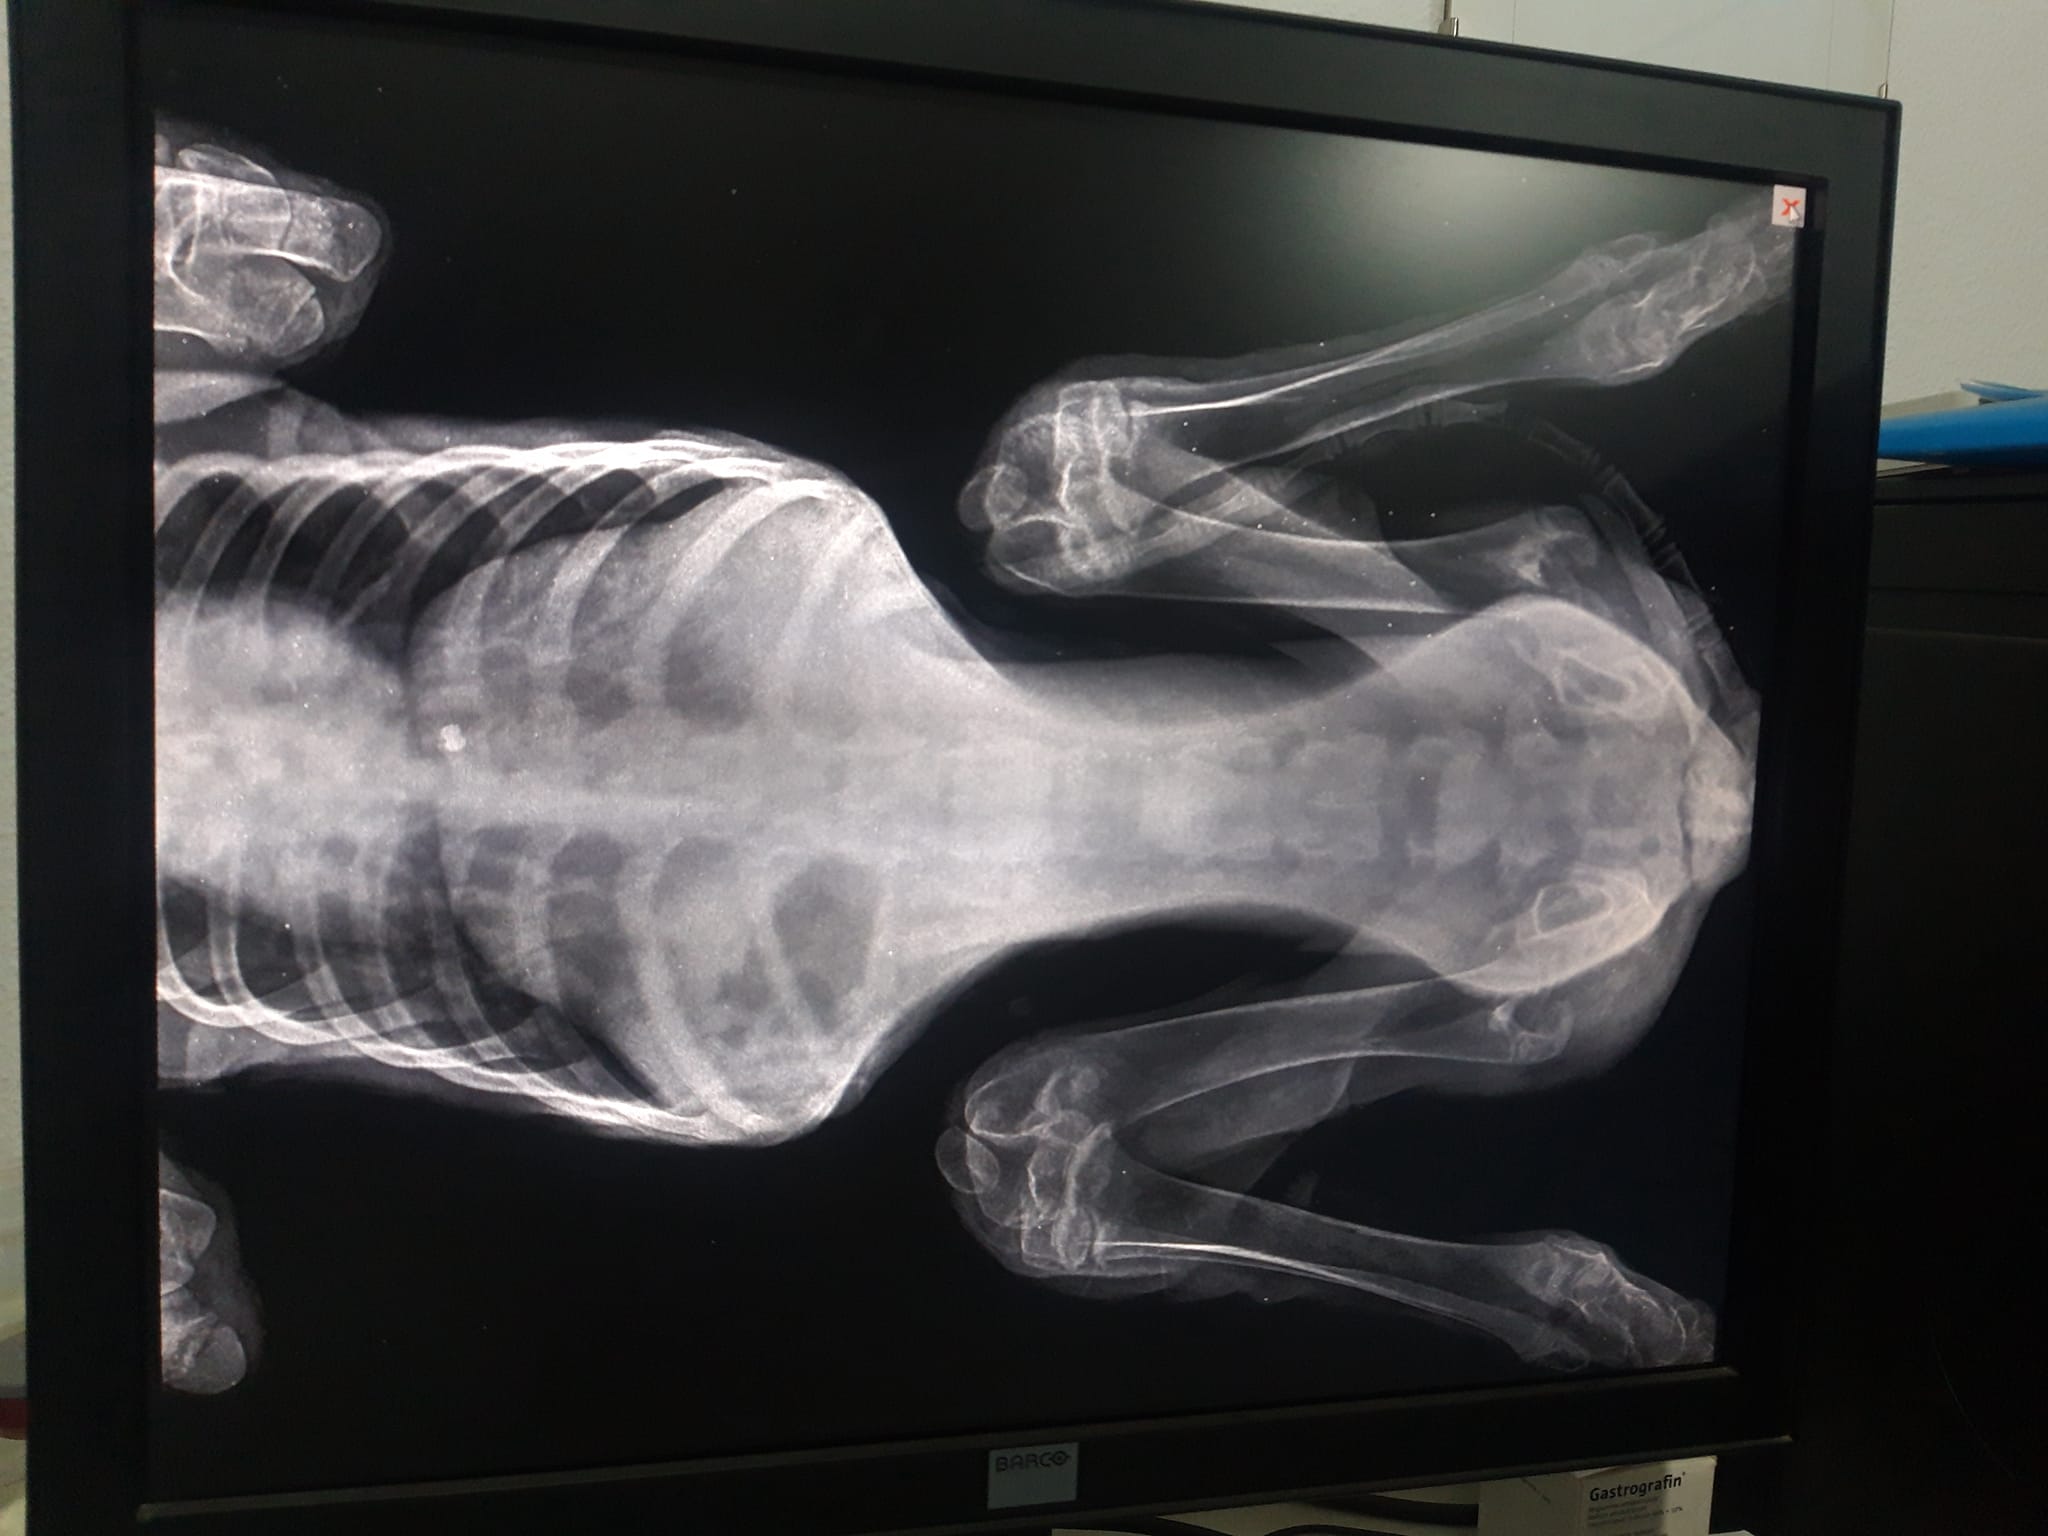

Στις ακτινογραφίες που διενεργήθηκαν ανευρέθηκε βλήμα αεροβόλου όπλου στη θωρακική κοιλότητα οπισθοστερνικά, έντονα ελαττωμένη οστική πυκνότητα ιδιαίτερα στα οπίσθια άκρα, αξιοσημείωτη χαλαρότητα αμφοτερόπλευρα και στα δύο γόνατα πού συνάδει με εικόνα ρήξεως πρόσθιου χιαστού. Στην ουσία όπως θα δείτε και στις ακτίνες μετά από ένα σημείο το στο σχεδόν παύει να υπάρχει, αν όχι από όταν γεννήθηκε τότε στην πορεία το ζώο όσο πιο ατρωφικο γινόταν το οστό τόσο τον οδηγούσε στην κατάσταση που είναι τώρα. Ο Αslan έχει 10% πιθανότητες όχι να περπατήσει αλλά να σταθεί, παρόλα αυτά δεν θα τα παρατήσουμε αφού έχει μια ζωντάνια και μια θέληση για ζωή που θαυμάζω μετά όλο αυτό που του συνέβη στους 5 μήνες της ζωής του ... Θα ακολουθήσουμε φαρμακευτική αγωγή για την θρέψη των οστών και σε 1 μήνα θα πρέπει να πάμε ξανά να δούμε πως πάμε! Για όποιον θέλει να βοηθήσει αυτοί είναι οι λογαριασμοί του κτηνιάτρου κ Νίκου πατσινακιδη.